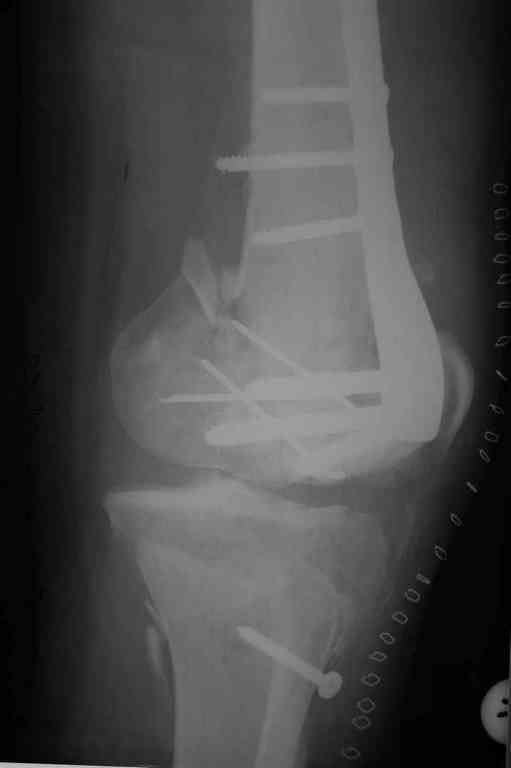

Re: Последствия открытого перелома дистального отдела бедра

Коллеги фиксатор Numelock II